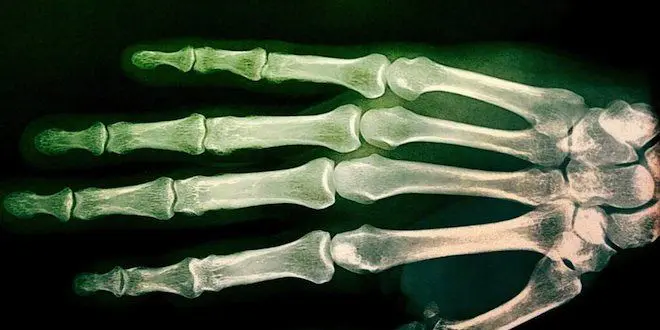

Suite à cette décision, la défense a déposé une QPC visant l'article 388 du code civil. Celui-ci encadre depuis 2016 le recours à ces examens radiologiques – souvent de la main ou du poignet – pour déterminer l'âge d'un jeune. Son avocate, Isabelle Zribi, a souligné que le recours à ces tests non "fiables" "porte atteinte à la protection de l'enfance et au droit à la santé et à la dignité" des migrants mineurs.

Utilisés dans de nombreux pays européens pour déterminer l'âge des jeunes migrants lorsqu'un doute subsiste, les tests de maturité osseuse sont très critiqués depuis des années, notamment par les associations d'aide aux migrants et certains médecins et professionnels de la justice. En cause : leur caractère obsolète. En effet, ils sont basés sur des données statistiques collectées dans les années 1930-1940 sur une population américaine et bien portante. En outre, les résultats pour cette population était déjà associée à une importante marge d'erreur, d'au moins 18 mois pour les 16-18 ans – qui est précisément la tranche d'âge concernée par ce type de tests.